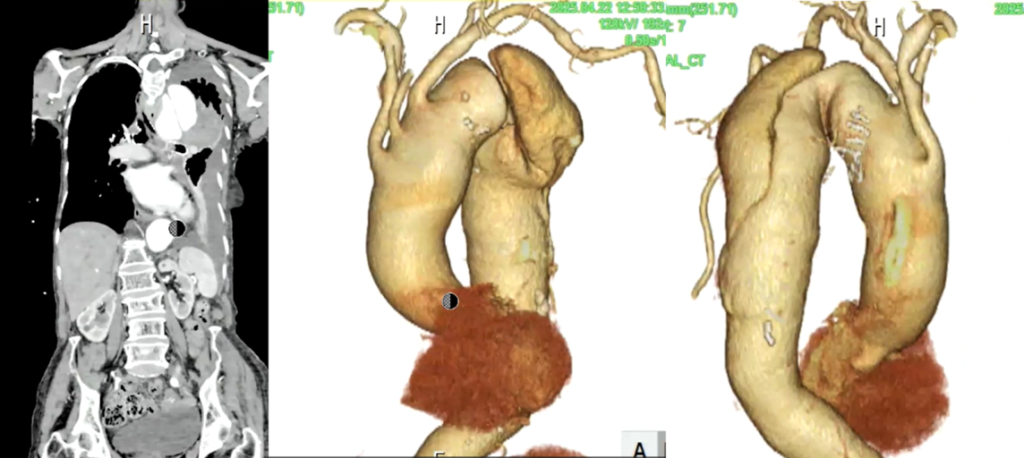

左肺に胸水を認めます。

大動脈が上行~下行まで拡張しています。

胸部大動脈の著明な拡張と、その周囲に高吸収域を認める(大動脈破裂、contained ruptureを示唆)。

大動脈が大きいのと周囲に高吸収域を認めます。high attenuating crescent signと言われるもので、

これを見た時には大動脈の破裂を疑うべきです。やっぱり寝台から下ろすのはちょっと良くないかなと思います。

大動脈というのは基本的に横断面では丸いものなので、この辺縁を追っかけていくと一部が突出っていうのは異常な突出なので、ここはもう出血・血種がここにできているんじゃないかなっというのは想像できると思います。

あと、胸水も普通の胸水とは違って凹凸状に、肺を押すような感じで、CT値も若干高いことから血性胸水なの かもしれないというのを推測することができます。

この症例はimpending ruptureではないんですよね 。もうすでに破れてるcontained ruptureに一致します。破れてるんだけど肺が押してるという状況です。もうすでに破れそう切迫破裂じゃなくてすでに破れてるという状況なので 、そういうのも合わせて手術適用ないという判断がされたと考えます。